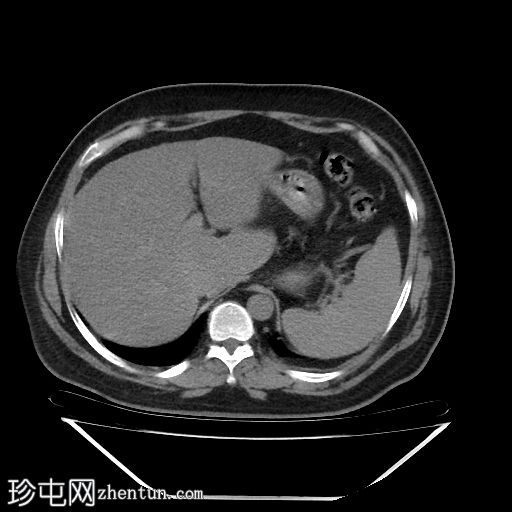

轴位增强扫描(门静脉期)

降结肠和乙状结肠可见多个小憩室,伴有少量小(亚厘米级)区域淋巴结肿大。周围脂肪和肠壁无明显增厚。

远端降结肠后壁可见一小(<15 mm)、局限性空腔,内含气泡,伴有不规则肠壁强化和轻度邻近肠系膜脂肪条索状改变。

未见脓肿、腹水、弥漫性气腹,提示IA期复杂性急性穿孔性憩室炎(局部穿孔)。